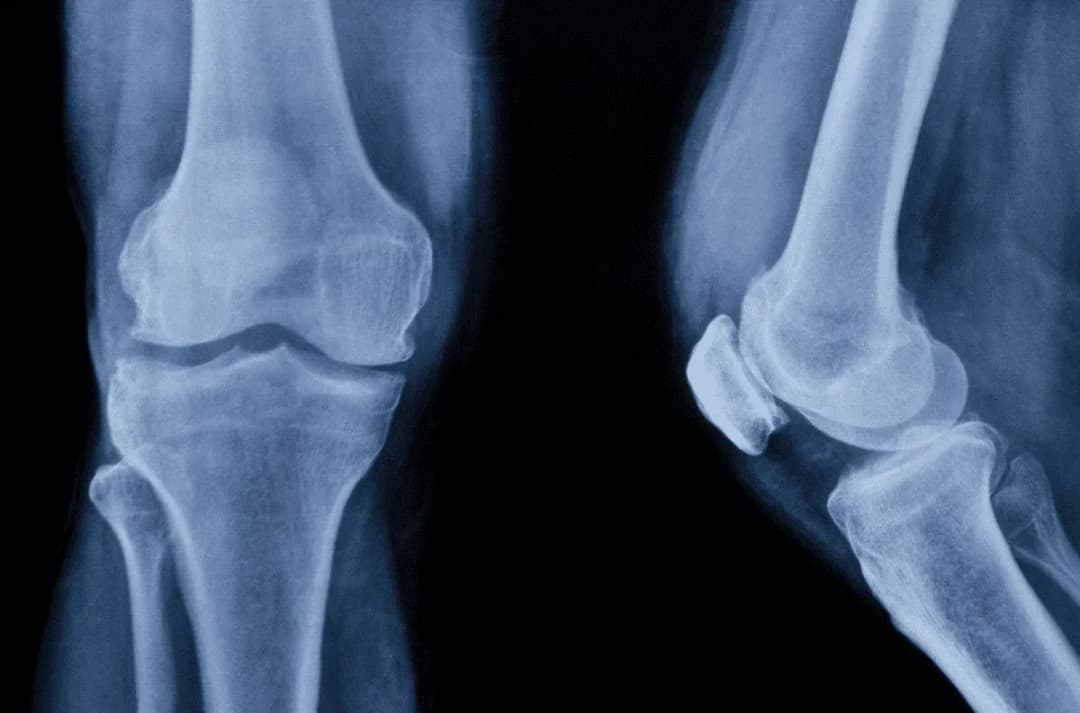

Odkryj sekrety anatomii kolana i zrozum złożoną budowę tego skomplikowanego stawu. Nasze kompendium zawiera kluczowe informacje o więzadłach, chrząstkach, mięśniach i anatomii stawu kolanowego, które pozwolą Ci lepiej zadbać o jego zdrowie.